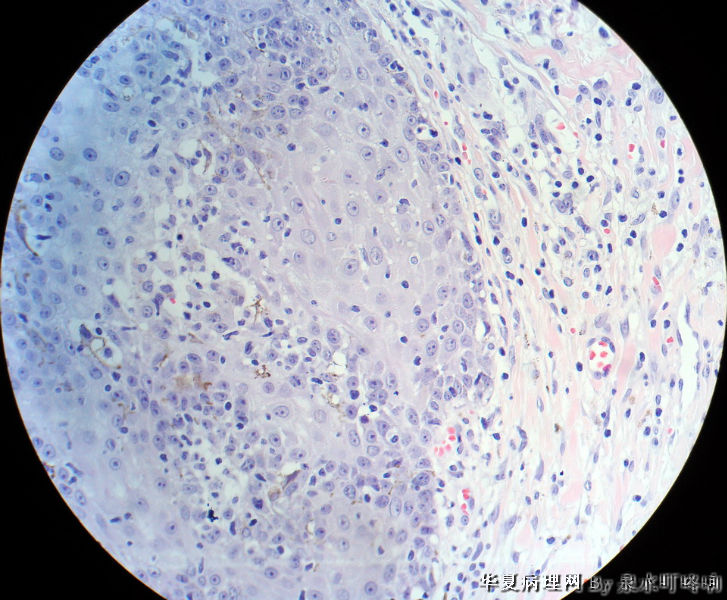

120316,发现头皮肿物一月余。

大体:灰黑色带皮组织一块,于皮瓣中央可见一直径0.7厘米灰黑色肿物,高出皮表0.4厘米,表面带有毛发,

切面灰白,质中。

角化棘皮瘤

图像符合脂溢性角化病。

也支持脂溢性角化病,激惹型还是乳头型?

典型的脂溢性角化病,未见病毒感染的空泡细胞,不是寻常疣

倾向脂溢性角化病(上皮角平坦)。  未见病毒感染的空泡细胞,也未见明显上皮角辐辏现象不考虑寻常疣